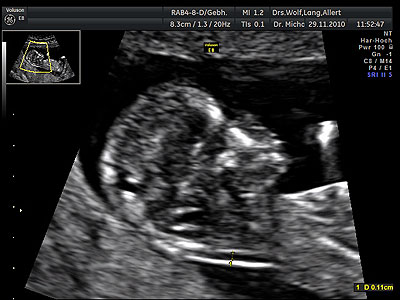

Der Ultraschall in der Schwangerschaft ist ohne Risiken für Ihr Kind. Nach den Mutterschaftsrichtlinien ist drei mal eine Ultraschalluntersuchung zur Überwachung der kindlichen Entwicklung vorgesehen.

Mit Hilfe des Ultraschalls können eventuell vorhandene Entwicklungsstörungen und Fehlbildungen des Kindes frühzeitig erkannt werden und so rechtzeitig notwendige Therapien und erweiterte Diagnostik eingeleitet werden. Es lassen sich mit unseren modernsten Ultraschall-Geräten auch Doppler-Untersuchungen durchführen, die Hinweise auf eine Plazentafunktionsstörung geben können.